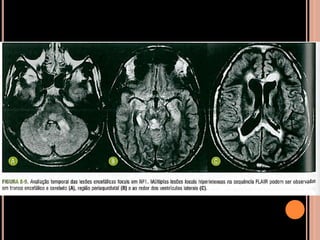

 ENCÉFALO

Túberes corticais;

Nódulos subependimários;

Astrocitoma subependimário de células

gigantes(ASCG);

Lesões de substância branca por distúrbios de

migração neuronal;

 Outras manifestações raras:

Cistos gliais, aneurismas cerebrais, hidrocefalia,

cistos de aracnoide, disgenesia de corpo caloso,

esclerose mesial temporal;

Achados de imagem

Achados de imagem – Ressonância magnética

 Recomendações

RM: método de escolha;

anual em paciente com CET e nódulos

subependimários adjacentes ao forame de Monro,

parcialmente calcificados e com impregnação pelo

Gd (crescimento e obstrução)  favorece ASCG e

indica cirurgia precoce;

TC sem contraste: só para ver nódulos

subependimários calcificados;